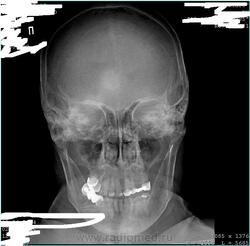

ППН для глазной операции, пациентка около 70 лет, пока с ней не разговаривала. Есть ли костный дефект правой височной кости или такая установка?

По первому случаю: нет не установка, состояние после резекционной трепанации черепа.

А что за кружок? Дефект ближе к лобной.